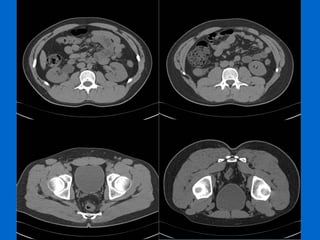

Estudio de elección:  UROTC   Fases: sin contraste con contraste: arterial, portal y eliminación que permite evaluar la hematuria con un único examen. Fase sin contraste: litiasis. Fase arterial:  alteraciones del parénquima (masas), evaluación de otros órganos abdominales Cortes finos en fase tardía:  distensión del sistema excretor y uréteres con contraste para evaluar patología uroepitelial (95% sensibilidad en detección de patología maligna del uroepitelio)  UROTC:  evalúa vejiga pero tumores planos difíciles de observar.  equivale a 4 pielografías de eliminación, > 10 mSv